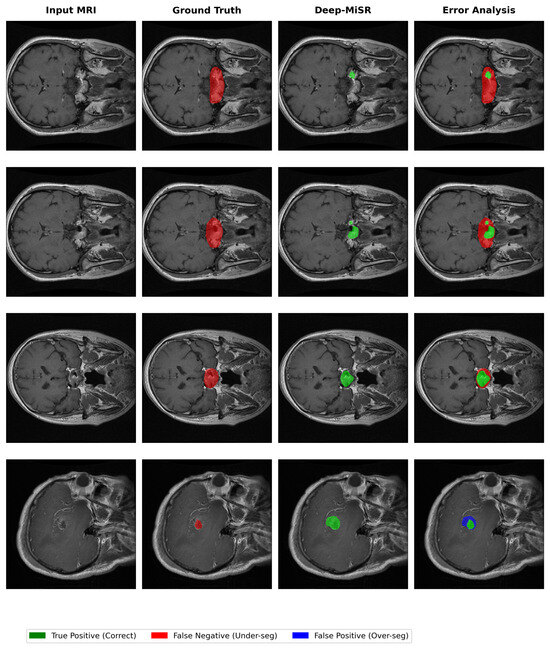

Deep-MiSR: Multi-Scale Convolution and Attention-Enhanced DeepLabV3+ for Brain Tumor Segmentation in MRI

by Md Parvej Mosharaf, Jie Su and Jing Zhang

Appl. Sci. 2026, 16(8), 3900; https://doi.org/10.3390/app16083900 - 17 Apr 2026

Accurate brain tumor segmentation in magnetic resonance imaging (MRI) is essential for diagnosis, treatment planning, and therapy monitoring. Conventional deep learning models often struggle with large variations in tumor shape, size, and contrast, as well as severe foreground–background imbalance. To address these challenges, [...] Read more.

Accurate brain tumor segmentation in magnetic resonance imaging (MRI) is essential for diagnosis, treatment planning, and therapy monitoring. Conventional deep learning models often struggle with large variations in tumor shape, size, and contrast, as well as severe foreground–background imbalance. To address these challenges, this study presents Deep-MiSR, an enhanced encoder–decoder framework built upon DeepLabV3+ with a MobileNetV2 backbone, tailored for single-modality contrast-enhanced T1-weighted (T1CE) MRI segmentation. Three complementary components are integrated into the architecture: mixed depthwise convolution (MixConv) with heterogeneous kernels within the atrous spatial pyramid pooling module for multi-scale feature aggregation, a squeeze-and-excitation block for adaptive channel recalibration, and R-Drop regularization that enforces prediction consistency via symmetric Kullback–Leibler divergence. The model was evaluated on 3064 T1CE slices from 233 patients drawn from the publicly available Nanfang Hospital brain MRI dataset. Deep-MiSR achieved a Dice similarity coefficient of 0.9281, a mean intersection-over-union of 0.8738, a precision of 0.8839, and a 95th-percentile Hausdorff distance of 7.69 mm, demonstrating consistent improvements over both the DeepLabV3+ baseline and all prior methods evaluated on the same data. Ablation studies confirmed that each component contributes independently, with R-Drop providing the largest individual gain. These findings demonstrate that combining multi-scale convolution, channel attention, and consistency regularization constitutes an effective and computationally practical strategy for robust single-modality brain tumor segmentation. Full article

Show Figures

Figure 1